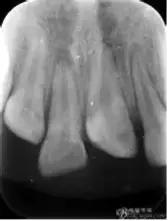

四条不同黑线显示牙齿折断的不同部位。

最下面那条仅仅是牙齿一小部分折断,一般不会对牙齿有很大损伤;下面第二条线,已经接近牙髓神经,可能会疼痛,还有可能出血,需要进一步治疗;第三条线折断更厉害,露在嘴里的牙冠基本都折断,只剩牙根了,这时就需要判断牙齿的状况,而采取相应的措施;最上面那条黑线就是牙根已经折断了,一般牙齿就无法保留了。但事实上,乳牙外伤最常见的是牙脱位(移位),所以很多家长会拿着孩子摔掉的牙齿,带着满嘴是血的宝宝来医院就诊。这个脱位也是分很多种的:牙震荡 牙齿没有松动、移位,仅仅是受到了撞击,刚开始会有咬上去疼痛的症状。半脱位 牙齿松动,但牙齿还在牙槽窝里位置没有改变。挫入 牙齿挫入牙槽窝,我们看上去就是牙齿比旁边的牙齿短了一截。脱位 牙齿从牙槽窝向口腔脱出,就是看上去比旁边牙齿长了一截。